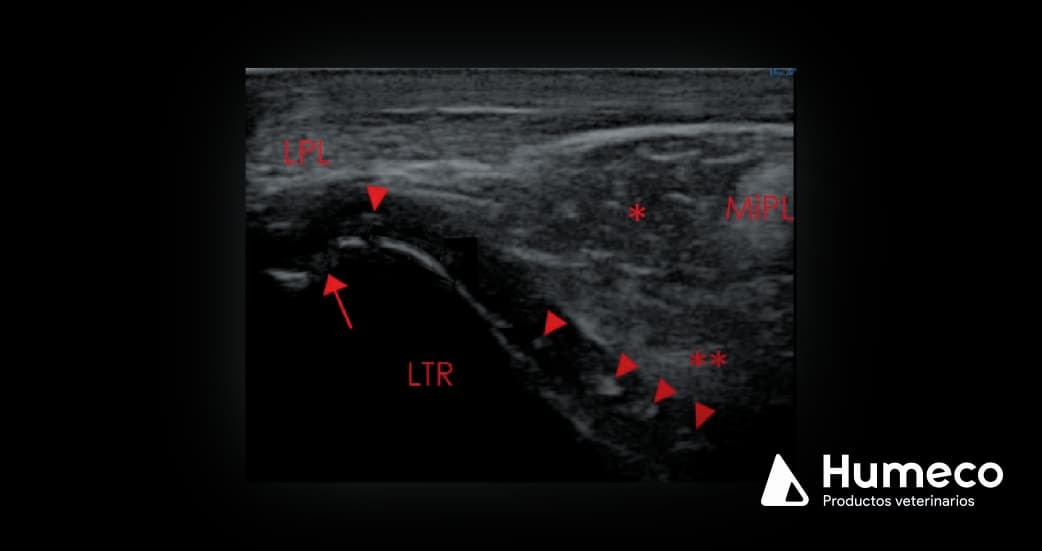

El cartílago articular normal es anecoico (negro) y regular, mientras que el cartílago afectado suele verse heterogéneo en ecografía, y puede contener regiones más fuertemente ecoicas (puntas de flecha, imagen 1,2).

El hueso subcondral subyacente puede ser irregular (flecha, imagen 1).

Imagen 2: Imagen longitudinal de la cresta troclear lateral (LTR) del fémur del mismo caballo que en la imagen 1. LPL= ligamento rotuliano lateral; puntas de flecha= regiones moderadamente hiperecoicas dentro del cartílago articular, consistentes con OCD.